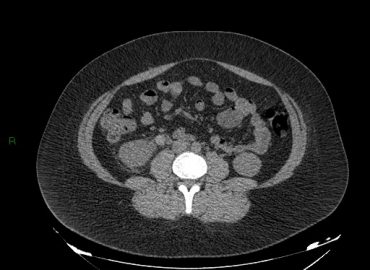

Paciente sexo femenino de 32 años que consulta por hematuria y dolor lumbar derecho